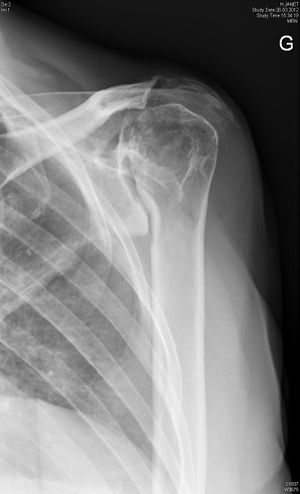

Malunited/nonunited proximal humerus fracture

Surgical options to address malunited proximal humerus fractures are determined largely by the existing deformity. They can be categorized broadly as humeral head-preserving techniques (e.g. osteotomies, soft-tissue releases and removal of bony protuberances) or humeral head-sacrificing techniques. Amongst the latter, reverse shoulder arthroplasty proved to be the most reliable.

Reverse shoulder arthroplasty for malunion of proximal humeral fracture. A) Anteroposterior radiograph of a malunited proximal humerus fracture; B) post-operative radiograph of the fracture sequelae treated with reverse shoulder arthroplasty.